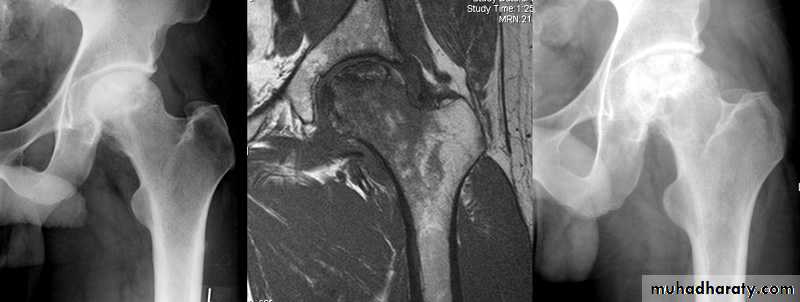

Changes are seen in the feet of diabetics with peripheral neuropathy.A vascular ( a septic ) necrosis :

Avascular necrosis , also known as osteonecrosis , is where there is death of bone due to interruption of the blood supply.The plain radiographic features including :

1. Increase density of the subchondral.

2. crescentic lucent line may be seen just beneath the articular cortex.

3.Articular cartilage space is preserved until degenerative changes super even .

4.In sub capital fracture of the femoral neck & fracture through the waist of the scaphoid bone , the femoral head & proximal pole of the scaphoid become fragmented & dense due to the ischemia .

MRI is imaging modality of choice for demonstrating a vascular necrosis and may show changes at time so early when radiograph may be normal .

A group of conditions , in which no associated cause for a vascular necrosis can be found . But the osteochondritis are now regarded as being due to impaired blood supply associated with repeated trauma .A-Perth's disease :

A vascular necrosis of the femoral head in children , is the most important example of the osteochondritis . the plain radiograph changes :

1.the earliest change is increase in density and flattening of the femoral epiphyses which later on progress to collapse & fragmentation.

2.epiphysis widened & consequently the femoral neck enlarge and may contain small cyst .

3.joint space is widened but the accetabulum not affected .

4.with healing, the femoral head reforms but remain permanently flattened & therefore responsible for OA in later life .